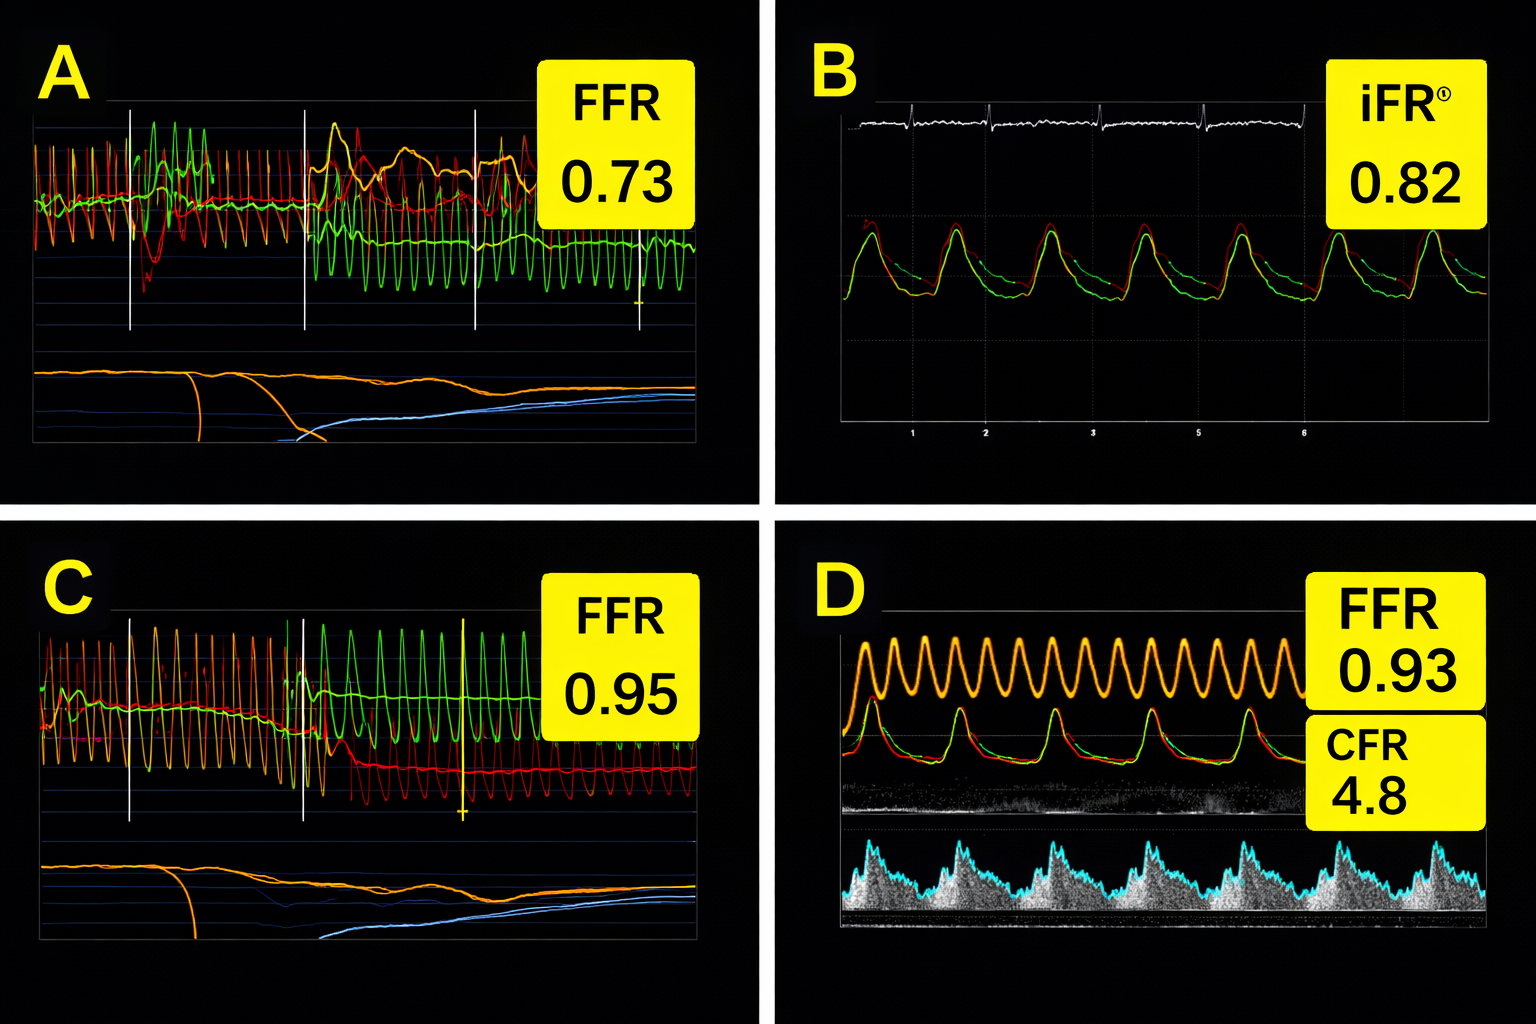

Coronary Physiology (Pressure & Flow Testing)

Not every narrowing seen on a scan causes symptoms or needs treatment. Coronary physiology tests measure how much blood is flowing past a narrowing and whether it is actually restricting blood supply to the heart muscle.

This is important to avoid unnecessary stents, ensuring treatment is only offered when it will genuinely help and it supports evidence-based, personalised care. This approach allows us to be precise rather than aggressive.